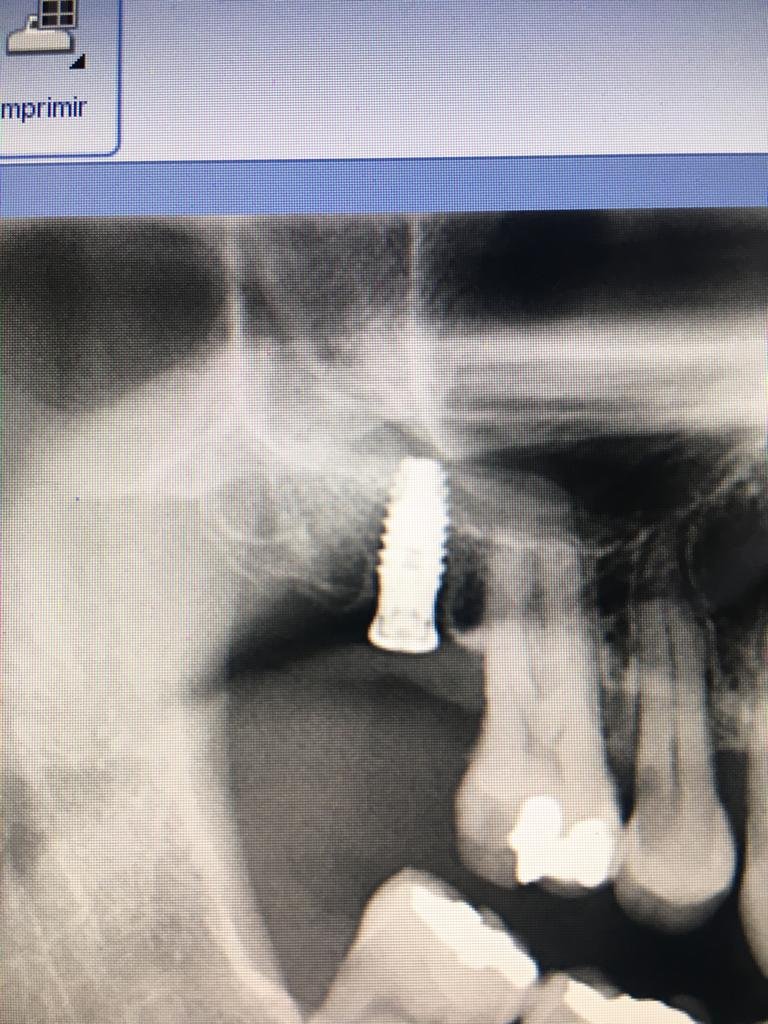

Que implante es el 22?

Hola!! Tengo un paciente con una corona cementada sobre el implante 22 que rota, y le tengo que hacer una nueva. Su dentista se retiró y no tenemos ninguna referencia. [...]